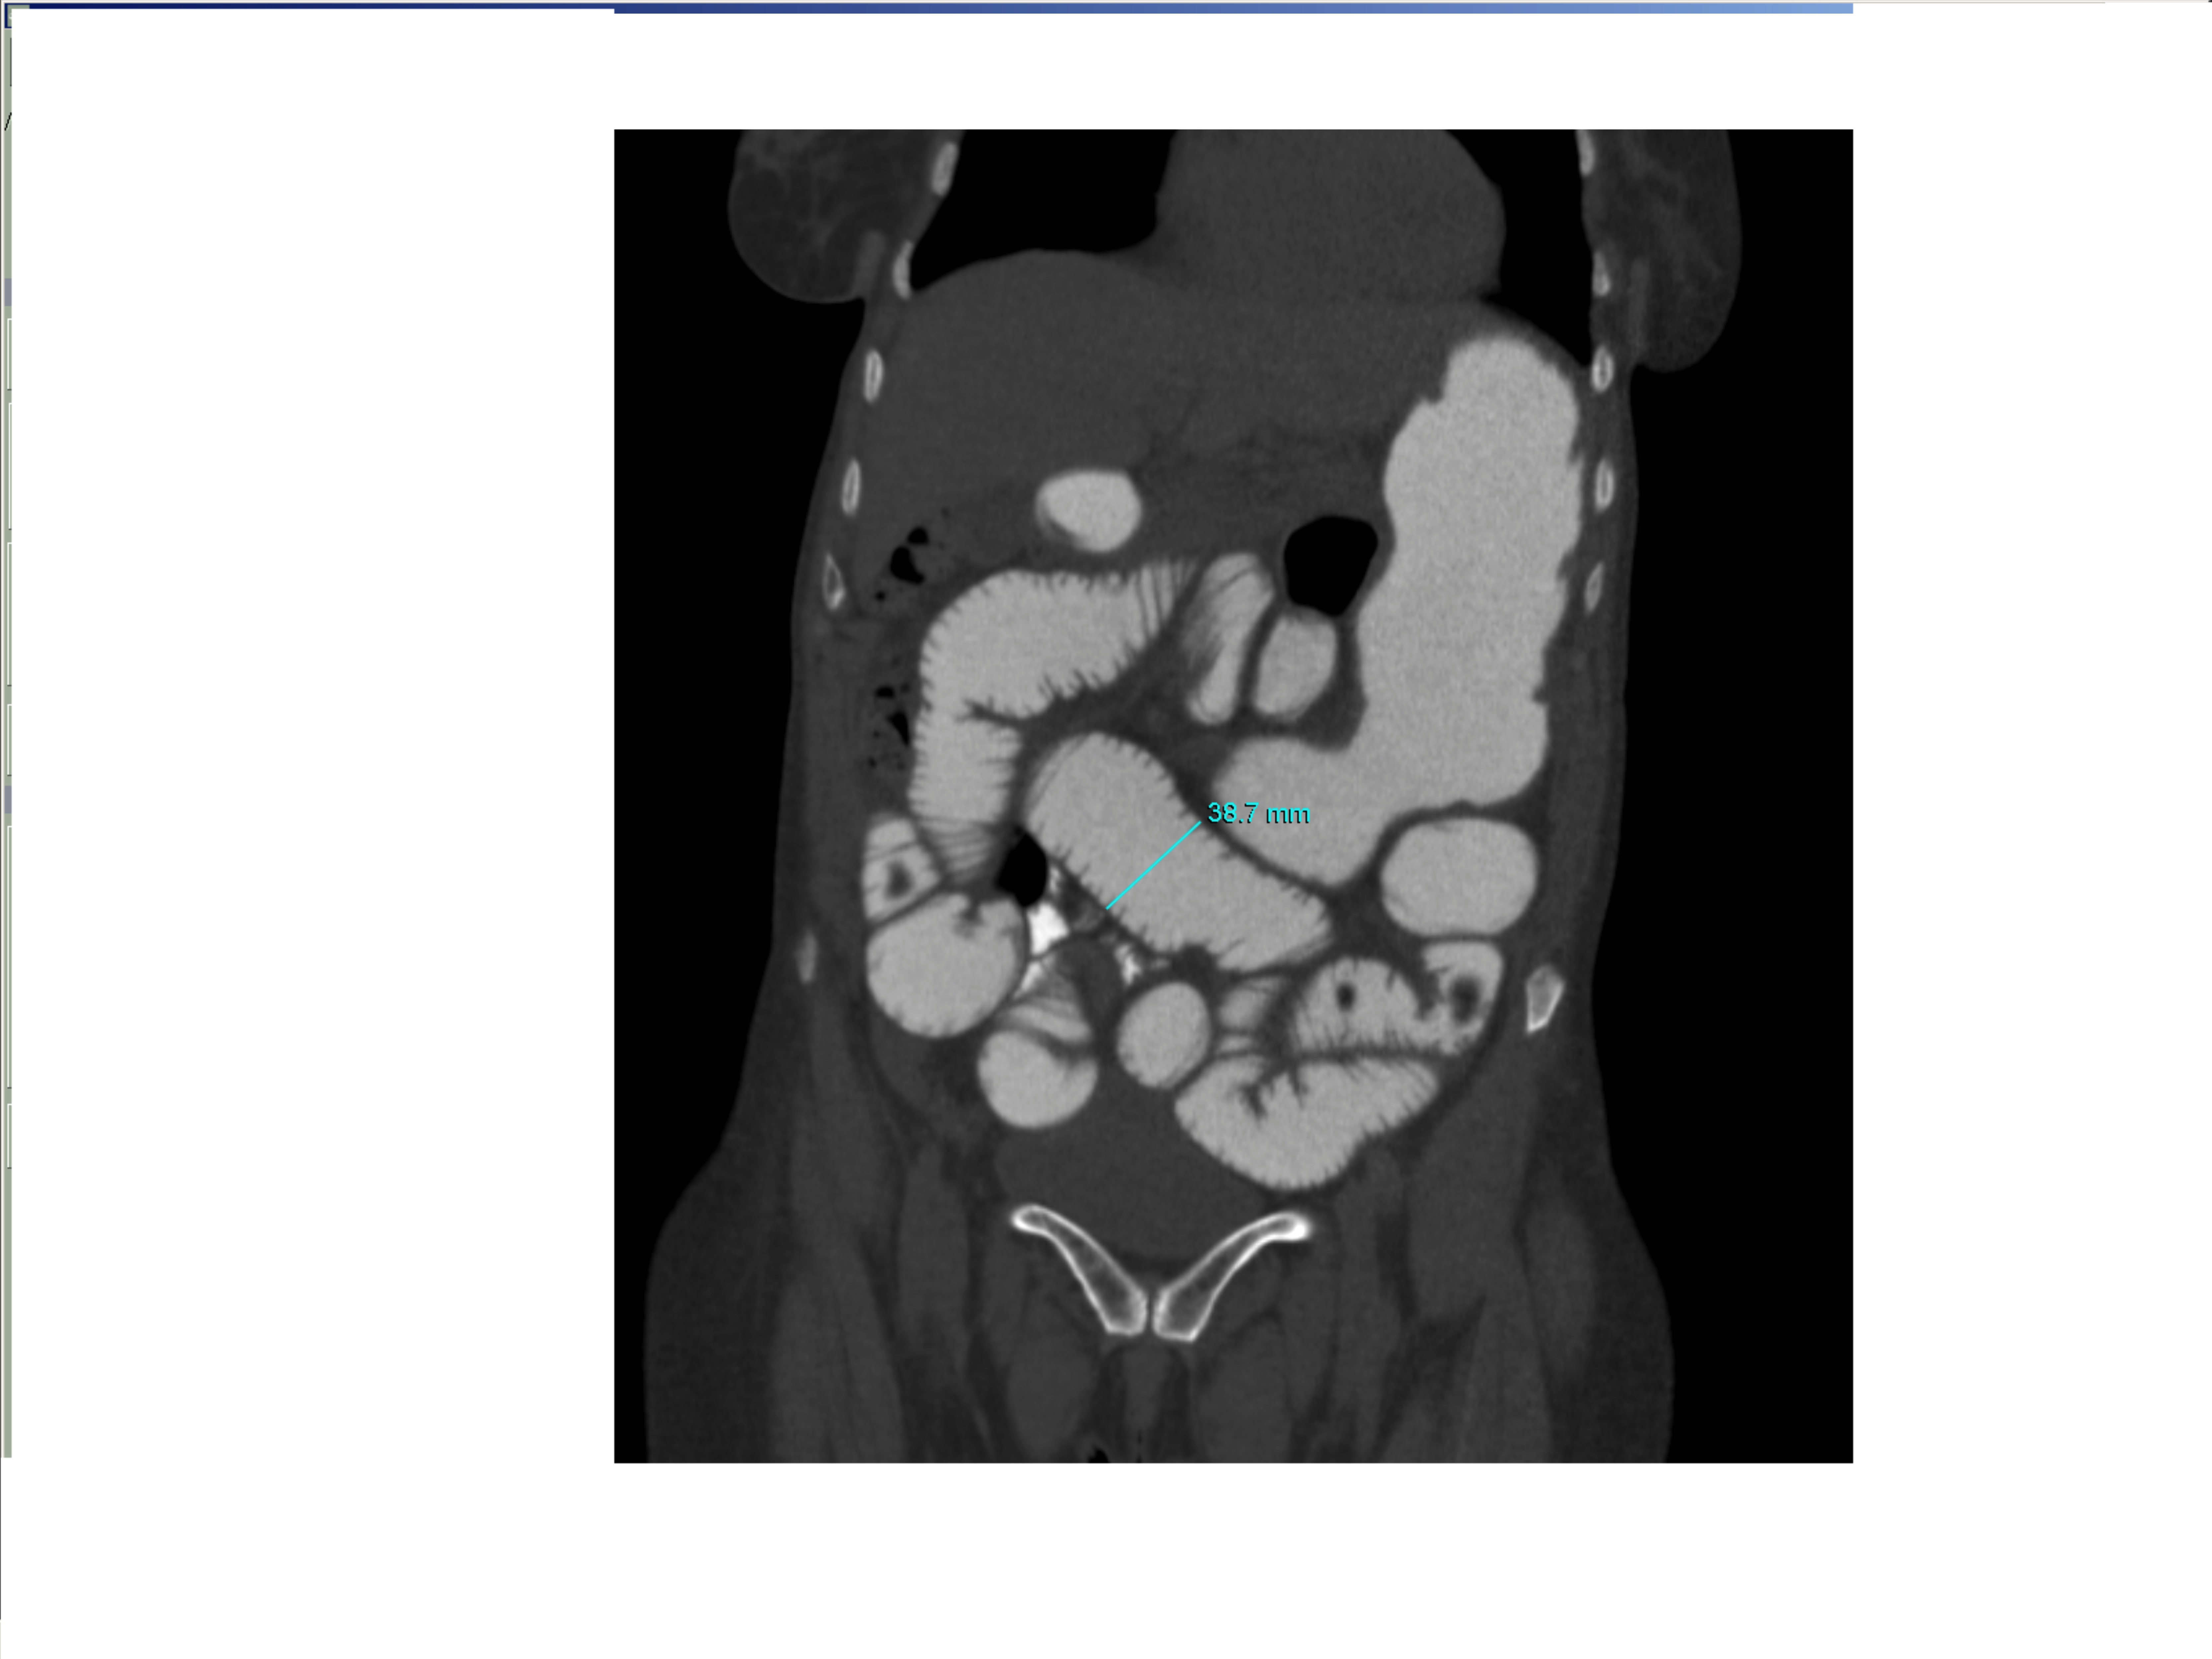

Small bowel obstruction is a common clinical presentation that presents a diagnostic conundrum. Over the last 2 decades, there has been a paradigm shift in the radiological investigation of small bowel obstruction (SBO) and in the indication for and timing of surgical intervention. Cross sectional imaging (predominantly computed tomography) has largely replaced the widespread use of radiographic small bowel follow-through studies as the imaging modality of choice for SBO. This article illustrates the current imaging modalities available for diagnosis of small bowel obstruction. (Full text available online at www.medpharm.tandfonline.com/ojfp) S Afr Fam Pract 2015; DOI: /10.1080/20786190.2014.977052